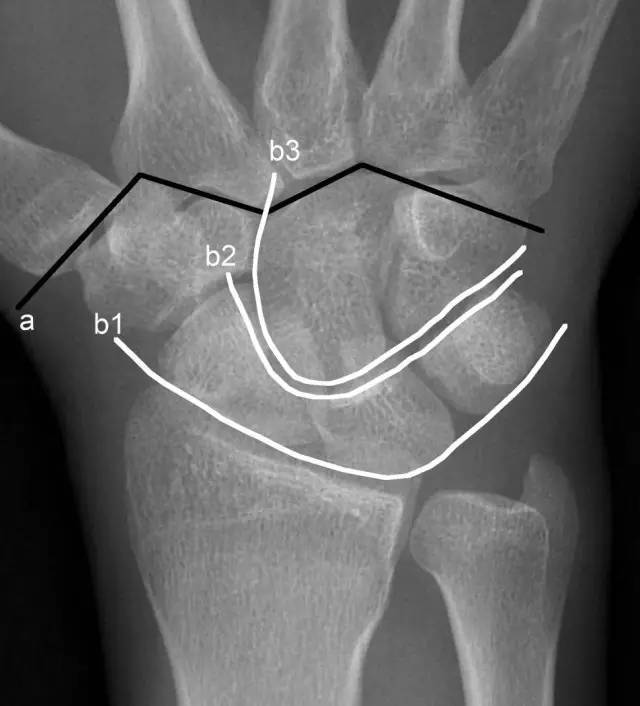

此外,腕关节关节面间弧线的连续性也是判断是否存在脱位的重要线索。如下图,若显示腕骨弧线不连续或各弧线不平行,或腕掌线M形结构消失,应高度怀疑腕关节不稳或脱位。

a. M形腕掌线 b. 腕骨弧线(Gilula线)